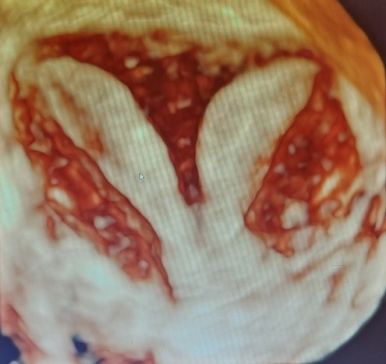

有鑑於陳小姐的生殖系統都很正常,2個子宮腔的大小相近,所以陳副院長在她進入試管療程之前,採行「陰道中隔切除術」,將夾在2個陰道中間約0.3mm厚的肌肉纖維切除,讓雙陰道合而為一,成為一條康莊大道,這樣先生與陳小姐在努力做人時,陰莖只會插入唯一的陰道,自然受孕的過程也會更順利、懷孕率也跟著提高。

當精子射出後會落在陰道子宮頸口處,再努力一路游過子宮頸、子宮,最終邁向由卵巢排出的卵子等候處:輸卵管,接著精卵相遇之後進而成為受精的胚胎,之後再順著輸卵管掉入子宮,試著在內膜完成著床,然後慢慢發育長成胎兒直至娩出。即,寶寶會選哪個子宮腔落腳,就端看當初受精的胚胎是位在哪一側輸卵管而定。